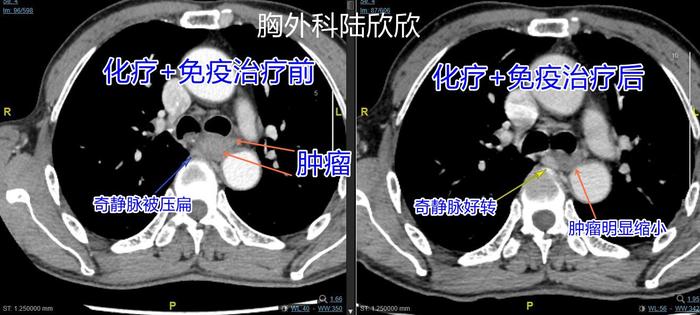

上图,左边的图是化疗加免疫治疗前的图,右边的图是化疗加免疫治疗后的图。橙色箭头指示的是请分叉水平的食管癌。可见,治疗前肿瘤右侧的奇静脉被压扁了。治疗后肿瘤缩小明显,右侧的奇静脉形状基本上复原